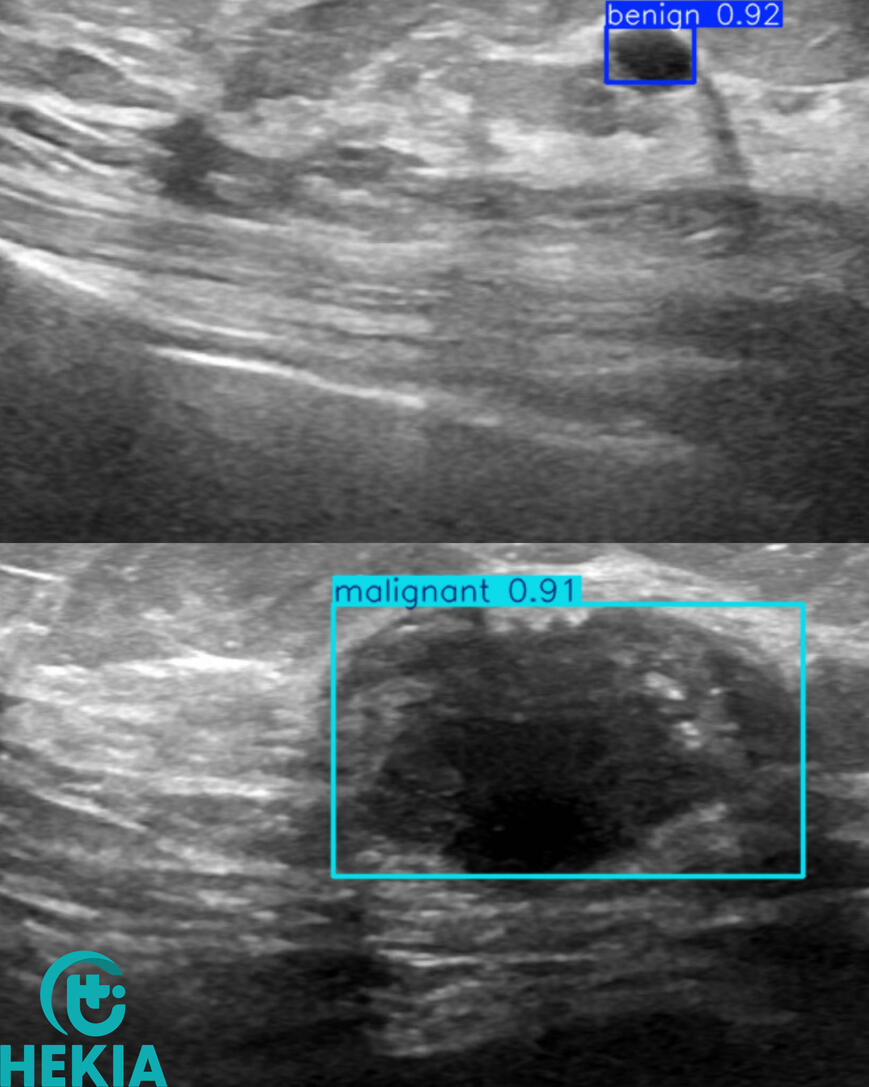

AI for ultrasound detection

Hekia is involved with Professor Fumery (CHU-Amiens-Picardie/UPJV) in the ECHIA-IBD1 project for real-time detection of Crohn's disease. The aim of this project is to speed up diagnosis by non-specialists in IBD ultrasound, make digestive tract ultrasound more accessible for monitoring Crohn's disease and UC activity, and improve patient outcomes.

Hekia continues to test its artificial intelligence solutions to detect other diseases such as lung, skin and breast cancers. These projects are in their early stages and will require new partnerships, so if you're interested or have a research project to propose, get in touch!